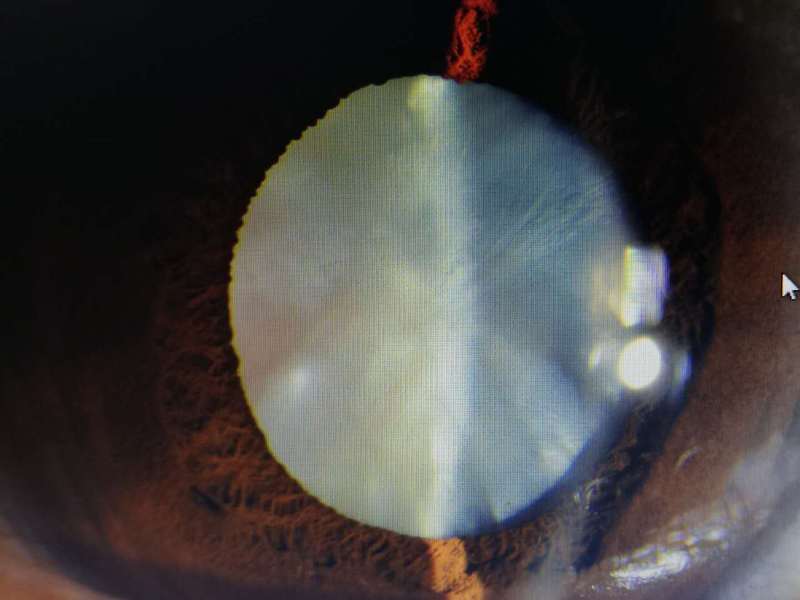

曾某,年齡不大,50歲,左眼白內(nèi)障。右眼完成白內(nèi)障手術(shù)已經(jīng)7-8年了,當(dāng)時(shí)手術(shù)難度大,患者自己擔(dān)心,所以一直不敢做左眼。眼部查:左眼視力手動(dòng)/眼前,晶體皮質(zhì)白色渾濁、膨脹,眼底不入。受我院醫(yī)務(wù)科主任之托,為她嬸嬸1周前完成手術(shù),順利,今天術(shù)后視力0.8,完美。